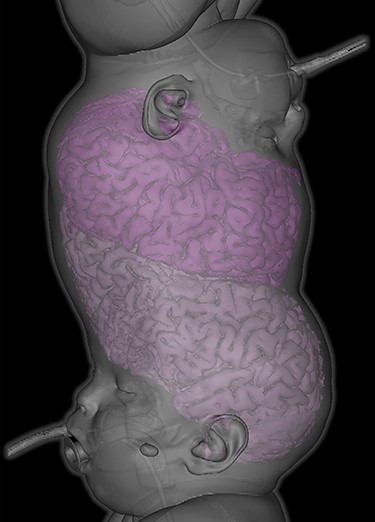

Handheld OCT acquisition. OCT image acquisition in lateral decubitus position under general anaesthesia using handheld OCT device.

Handheld OCT was also performed using the Envisu C2300 (Leica Microsystems, Wetzlar, Germany) with each twin in the lateral decubitus position (Fig. 4), demonstrating healthy foveae and no optic nerve head swelling (Fig. 5). All OCT parameters fell within the normal range for age [6]. Our OCT acquisition protocol has been recently described [7].